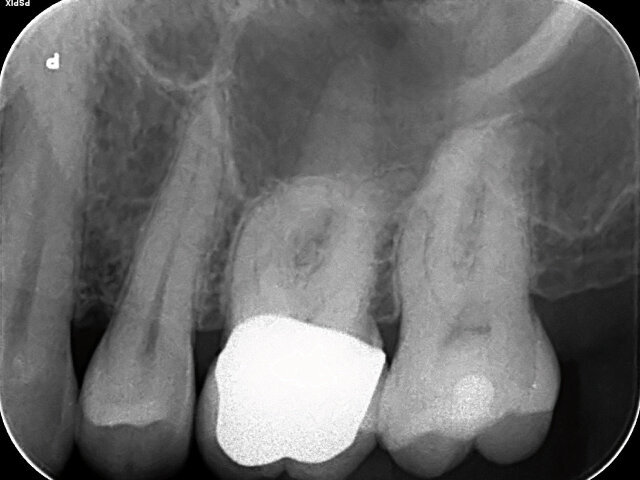

Pacient se ke mně dostavil s akutní bolestí v horním levém kvadrantu. U zubu 26 byla diagnostikována akutní apikální periodontitida a byl ošetřen v průběhu dvou návštěv. Rentgenový snímek ukázal, že meziobukální kořen měl výrazné zakřivení a distobukální kořen mírný esovitý tvar kanálku (obr. 1). Zub byl opatřen přesnou zirkonovou korunkou a byl proto vhodný co nejvíce konzervativní přístup k vytvoření kavity. Cylindrickým diamantovaným brouskem bylo otevřeno cavum pulpae a nalezeny vstupy do tří kořenových kanálků. Při jejich opracovávání byl použit 3% chlornan sodný.